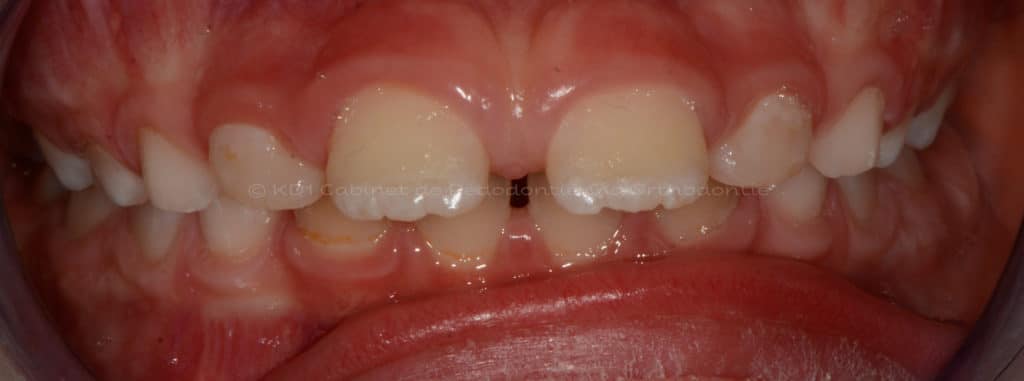

Correction des problèmes d’occlusion en dentition mixte, c.-à-d. à l’âge où l’enfant a des dents de lait et adulte, souvent entre l’âge de 7 ans et 9.5 ans. Le but de ces interventions n’est pas d’aligner les dents, car la dentition est en train de changer.

Cas #1 – Traitement avec un casque de traction maxillaire en dentition mixte (âge 8.5). Le but est de redresser les dents de devant (très penchées en avant) afin d’éviter les cassures de ces dents. Le recul de la dentition supérieure est possible avec ce dispositif extraoral.